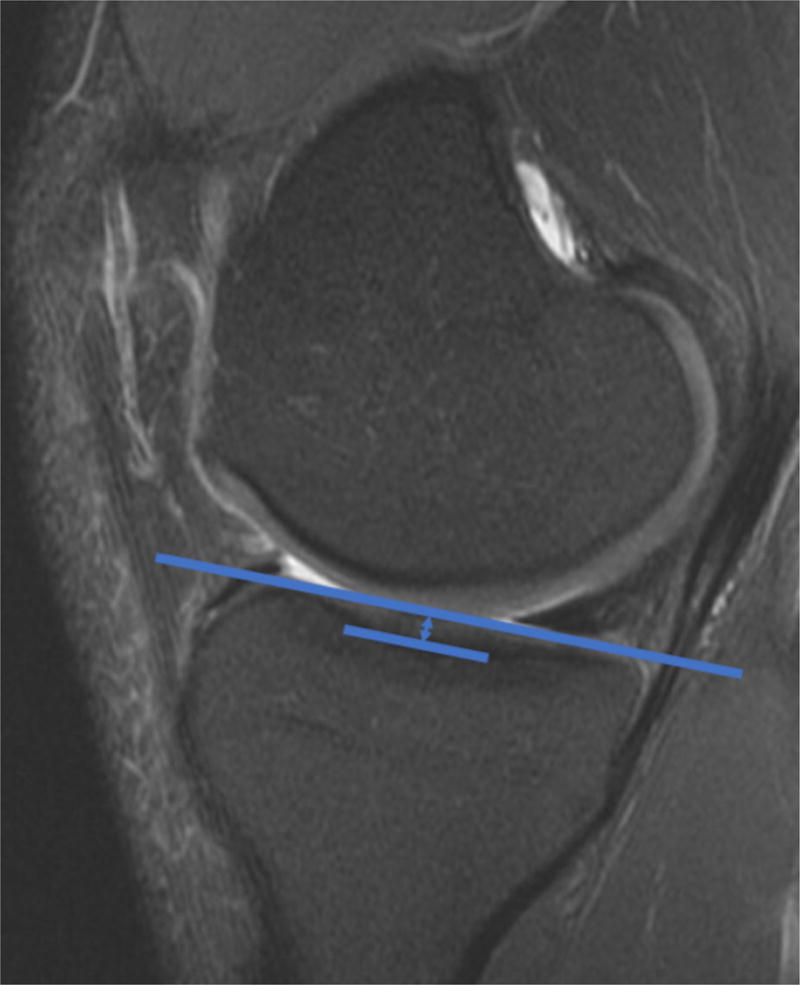

The depth of the medial tibial plateau has also been implicated in contributing to the risk of ACL injury. The medial plateau has a concave shape that allows for inherent congruity with the medial femoral condyle and is more constrained relative to the convex lateral plateau. Hashemi et al., measured the depth of the medial tibial plateau on MRI for 49 patients with ACL injuries and 55 subjects without ACL injury.23 A shallower medial tibial plateau was noted in patients with ACL injuries (Figure 2). This finding suggests that patients with ACL injury may have bone shape features, such as a shallow medial tibial plateau, that predispose to ligamentous injury, which may help to identify patients who may benefit from additional procedures in addition to ACL reconstruction, though this hypothesis would need further clinical and biomechanical testing.

Figure 2.

The depth of the medial plateau was shown by Hashemi et al23 to be associated with the risk of ACL injury. A shallow medial tibial plateau, measured as shown here on a sagittal MRI, may be associated with less articular congruity and greater risk of ACL injury.